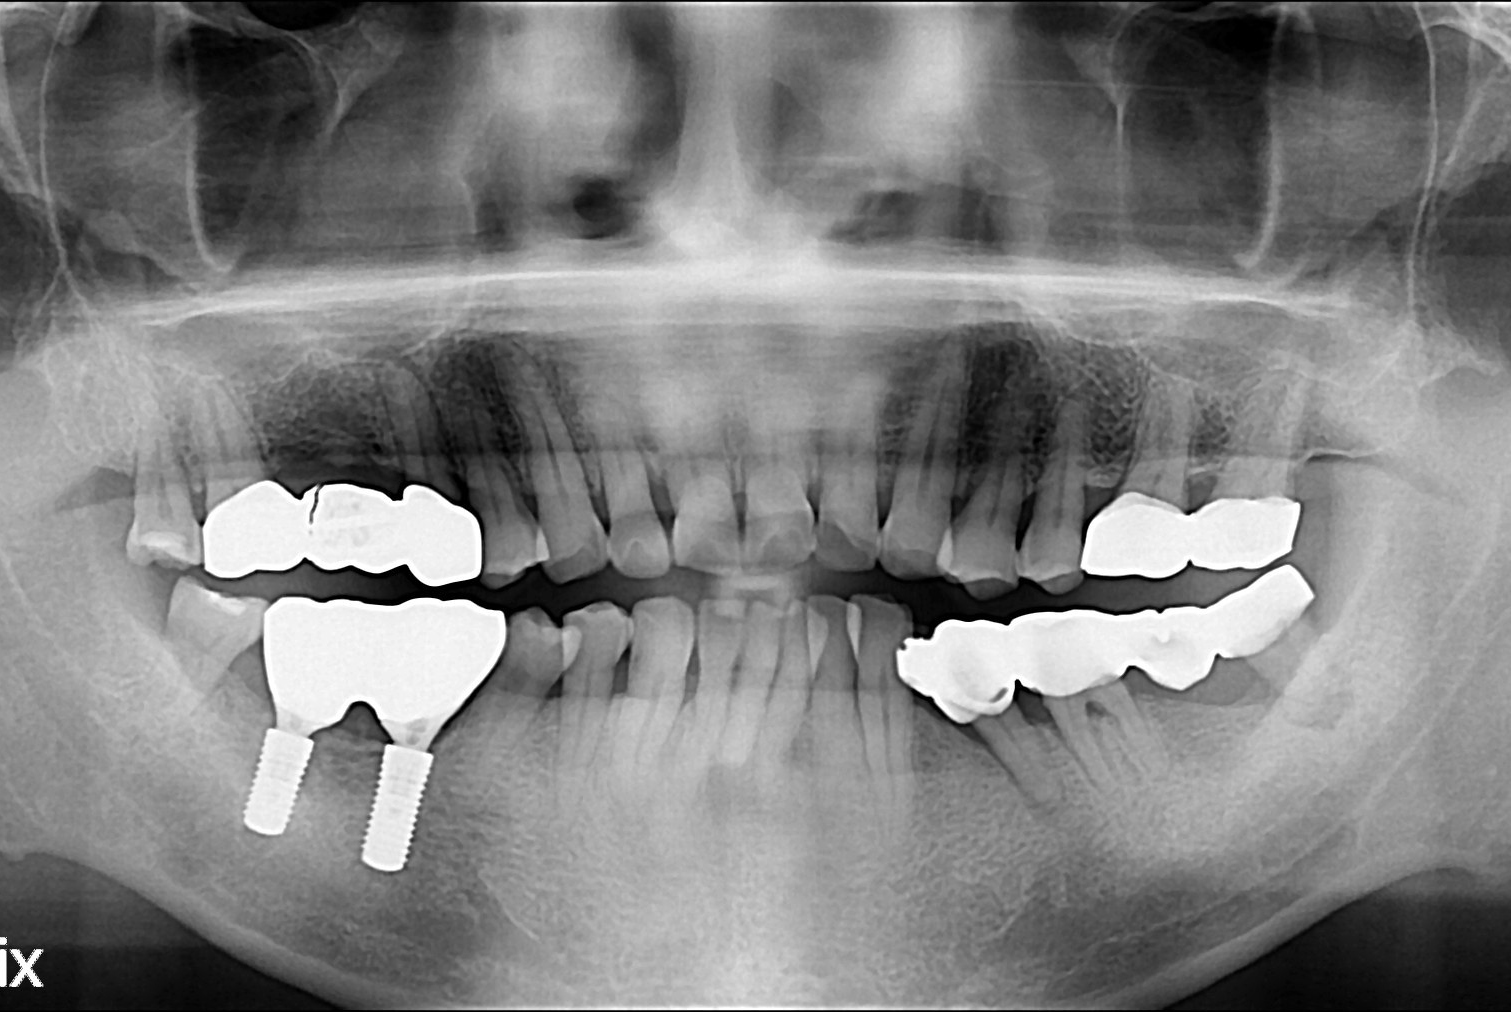

[임플란트] 임플란트

치료전 : 2018-06-15

세종치과는 많은 환자와 다양한 케이스를 바탕으로 항상 편안한 임플란트 수술을 제공하고자 노력하고,

오래동안 튼튼히 쓸 수 있는 임플란트 수술을 가장 큰 목표로 삼고 있습니다